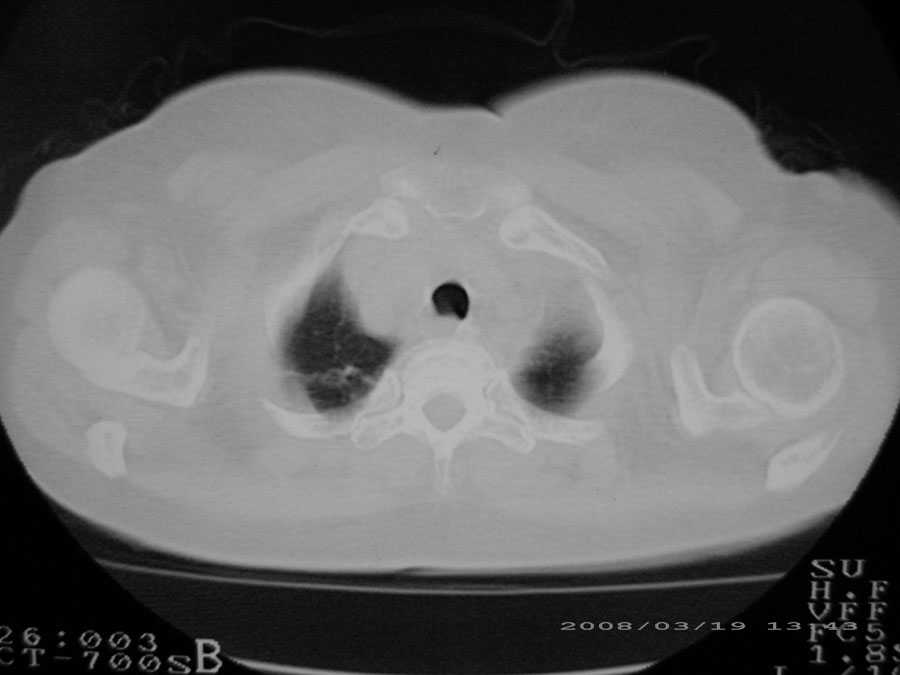

标题: CT13104:胸部大家看看啊,第一次发啊, [打印本页]

标题: CT13104:胸部大家看看啊,第一次发啊,

综合大家意见,结核、结节病、肺泡细胞癌均有可能,间质性肺炎暂不考虑,病灶纠集不明显,纵隔未见钙化淋巴结,尘肺可能性不大,但还是要密切结合临床诊断。

今天重新仔细看了看,矽肺确实不能除外,病灶主要表现为间质结节及纤维化。好好问问病史吧。